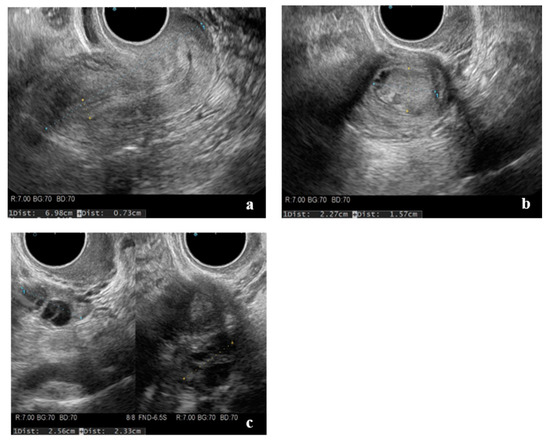

2. Case Presentation